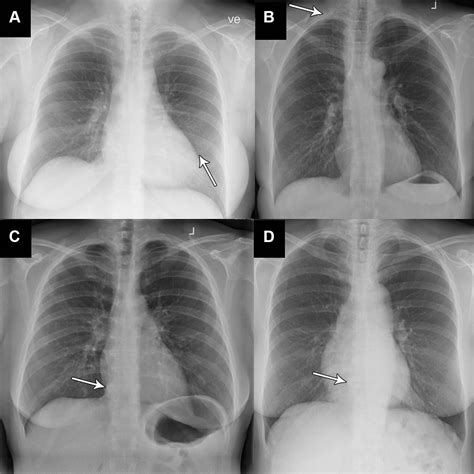

Certain findings on a chest X-ray are particularly important to recognize. Here are some key examples:

Consolidation

Consolidation refers to the replacement of air in the lungs with fluid, cells, or other material. It appears as an area of increased opacity on the X-ray. Common causes include pneumonia and pulmonary edema.

Pleural Effusion

Pleural effusion is the accumulation of fluid in the pleural space. It appears as a layer of fluid along the chest wall or as a meniscus sign on the lateral view. Common causes include heart failure, pneumonia, and malignancy.

Pneumothorax

Pneumothorax is the presence of air in the pleural space, causing the lung to collapse. It appears as a lucent area without lung markings. Common causes include trauma, spontaneous pneumothorax, and iatrogenic injury.

To illustrate the interpretation of abnormal chest X-rays, let’s consider a few case studies:

Case Study 1: Pneumonia

A 65-year-old patient presents with fever, cough, and shortness of breath. The chest X-ray shows consolidation in the right lower lobe. The patient’s history of recent travel and exposure to sick contacts suggests a bacterial infection. Further investigations, including blood cultures and sputum analysis, confirm the diagnosis of pneumonia.

Case Study 2: Lung Cancer

A 50-year-old smoker presents with persistent cough and weight loss. The chest X-ray reveals a 3 cm mass in the right upper lobe. A CT scan confirms the presence of the mass, and a biopsy reveals non-small cell lung cancer. The patient is referred to an oncologist for further management.

Case Study 3: Heart Failure

A 70-year-old patient with a history of hypertension presents with shortness of breath and peripheral edema. The chest X-ray shows cardiomegaly and pulmonary edema. An echocardiogram confirms the diagnosis of heart failure, and the patient is started on diuretics and other medications to manage the condition.